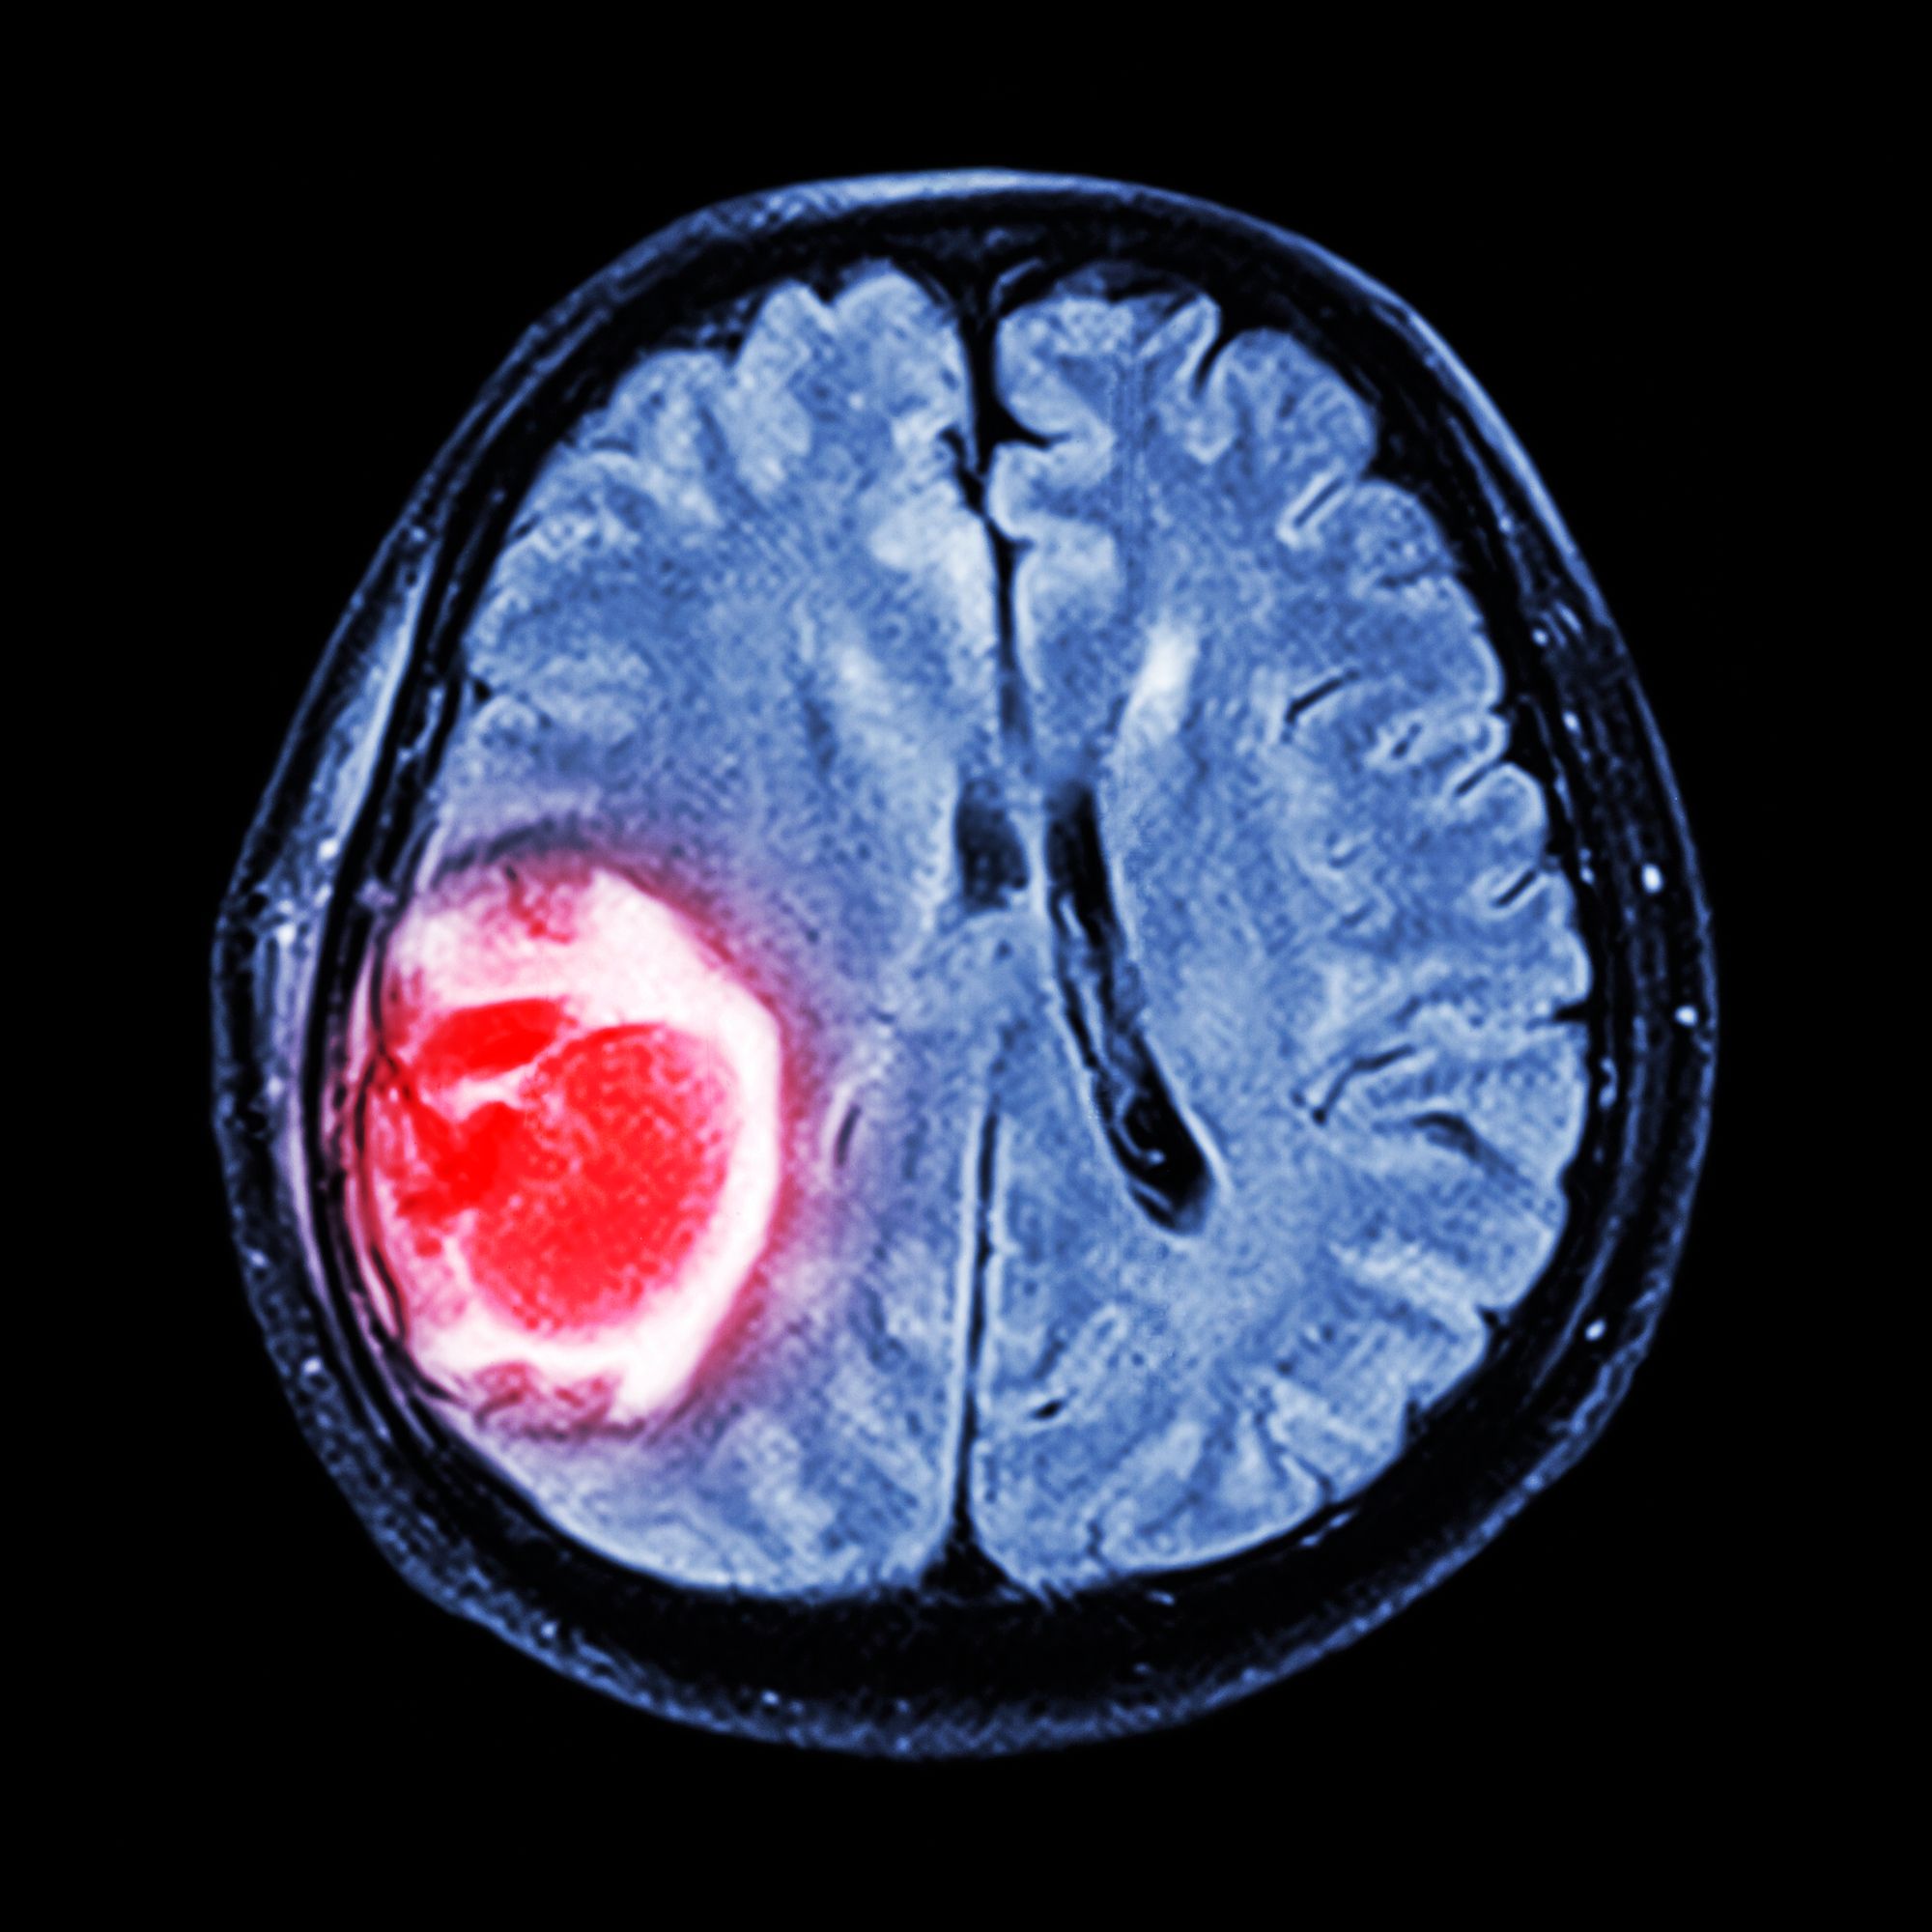

Nachrichten-Moderatorin stirbt an Hirntumor